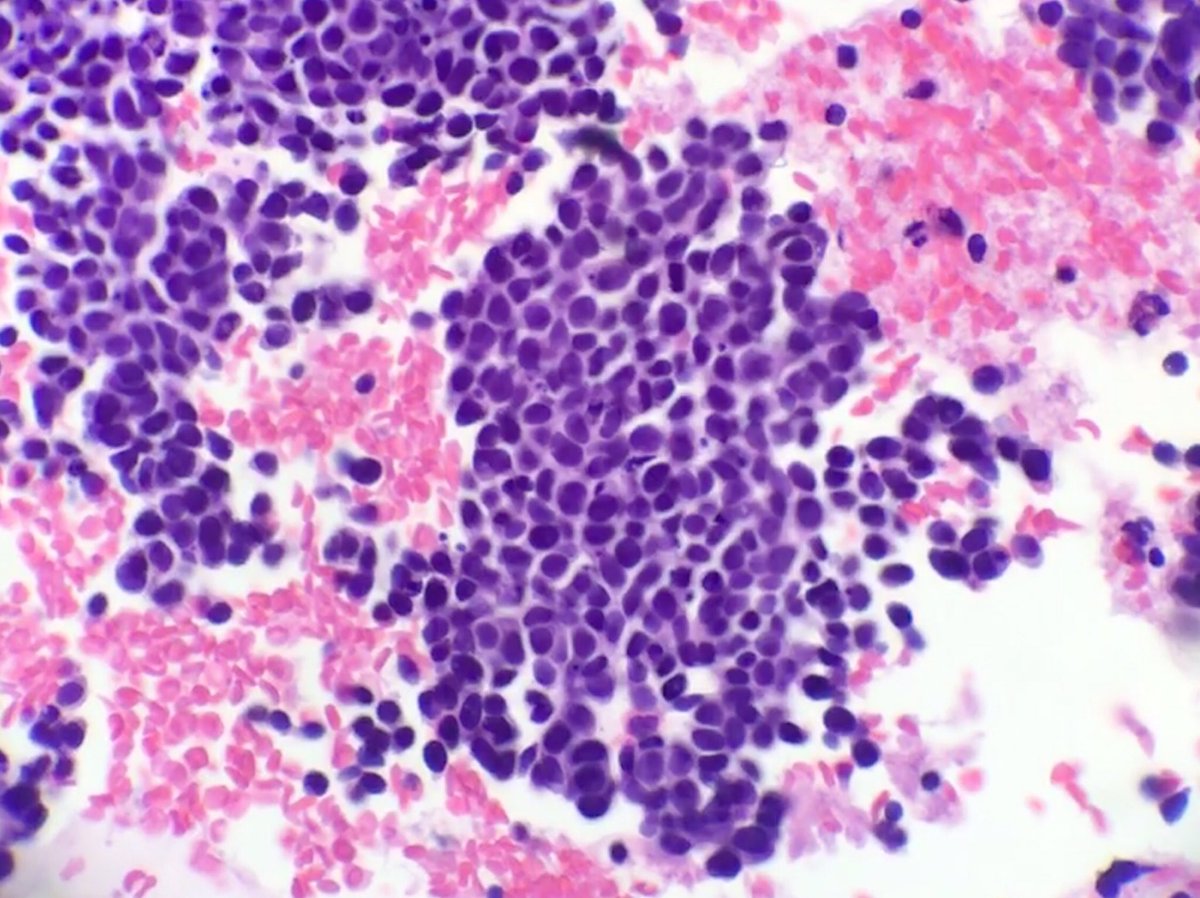

Young people with weakened immune systems can also develop merkel cell carcinoma. Mccs are dermally based tumors composed of small uniform round blue cells arranged in anastomosing cords, bands and clusters. Mathew ludgate mbchb, dept of dermatology greenlane hospital auckland, new zealand, 2005. The tumor developed in an area of extensive sun damage. Merkel cells are situated in the top most layer of the skin which is very near to the nerve endings that accept the touch sensation. Cancer occurs when cells begin to randomly divide and grow out of control. Merkel cell carcinoma (mcc) is a rare and aggressive skin cancer occurring in about 3 people per 1,000,000 members of the population. Merkel cell carcinoma typically affects older adults and the tumour usually starts in a sun exposed area such as the head or neck.

Aimi T Rothrock Md On Twitter Day 35 Merkel Cell Carcinoma On Cytology Cd56 And Nse Are More Likely To Be Positive Compared To Synapto And Chromo Cytopath Pathology Learningeveryday Https T Co Y2h1iz3jdw